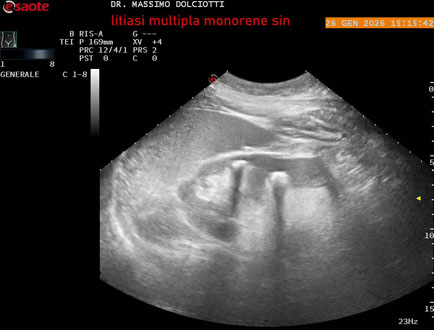

Data inserimento: 29/01/2026

Ecografia del: 26/01/2025

Strumento: Esaote MyLab Eight

Sonda: Conevx Multifrequenza 1-8 MHz

Età Paziente: M 78 anni

Motivazione dell'esame: follow up di litiasi al rene sinistro, in paziente sottoposto a nefrectomia destra.

Commento all'esame: le immagini ed il video documentano il rene sinistro in sede, di ecostruttura disomogenea per evidenza di multiple formazioni litiasiche al pielone superiore, delle dimensioni di 15,9 mm, al pielone medio di 17,5 mm e al pielone inferiore di 18,9 mm e morfovolumetria normale, con diametro bipolare di 115 (v.n. 90-120 mm) x 54 mm e parenchima renale dello spessore di 17 mm ( v.n. > 13 mm).

Conclusioni: litiasi multipla del monorene sinistro (multiple lithiasis of the left solitary kidney).

In collaborazione: Dr.ssa Marica Manfredi - Ancona, Dr. Ilir Qose - Ancona

Presentazione: Dr. Massimo Dolciotti - Ancona

Elaborazione digitale: Andrea Dini - Ancona